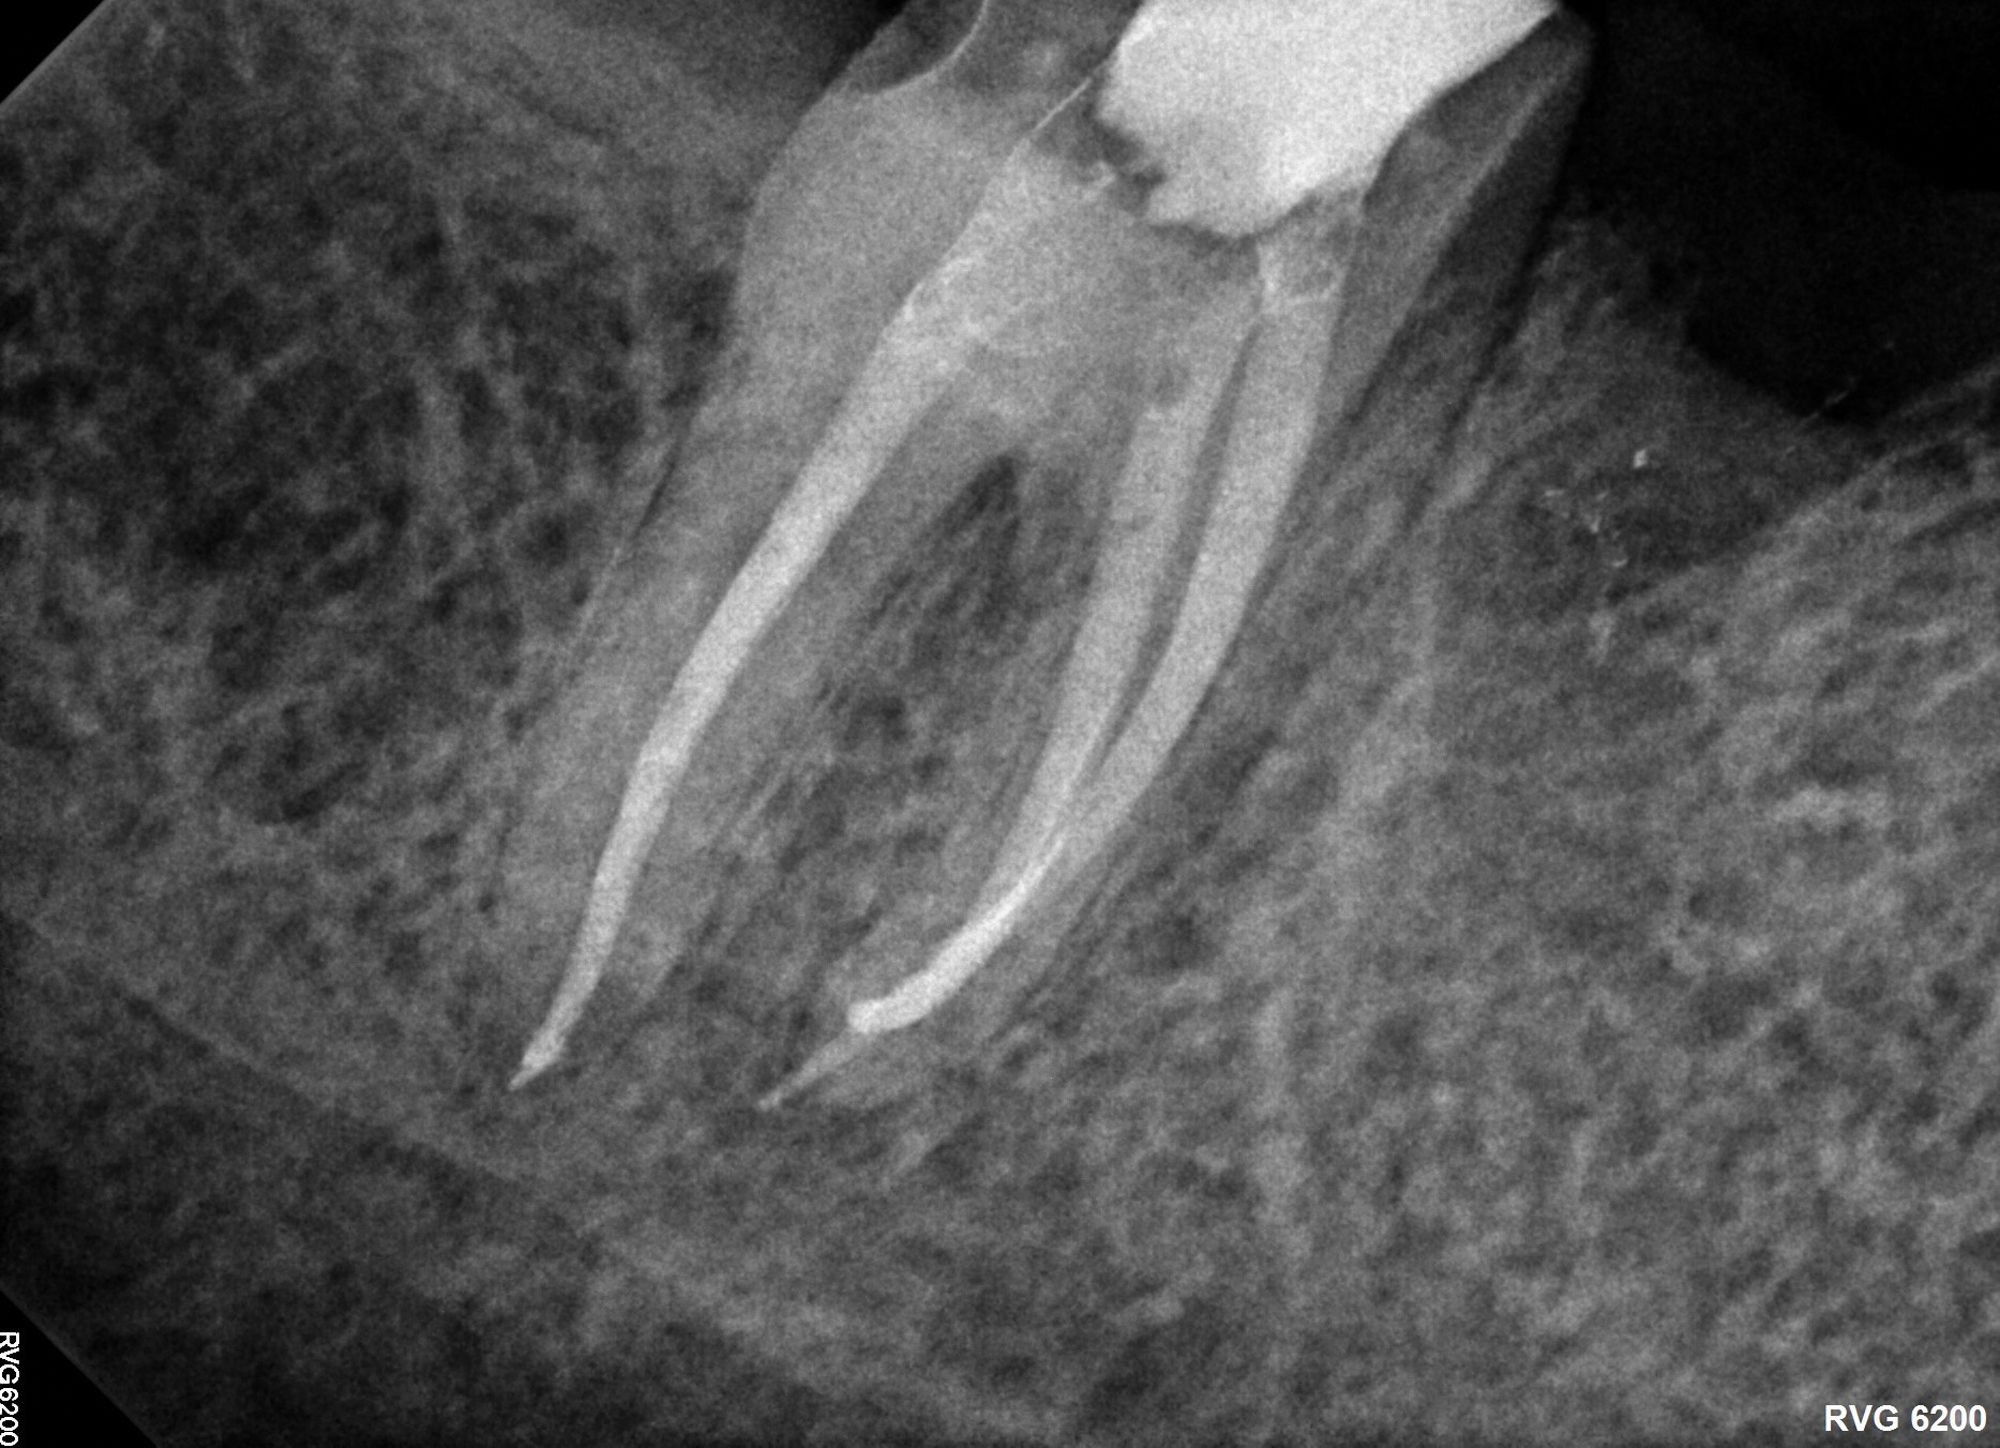

Figure 3A.

Figure 3B. Although vital pulp therapy was planned for tooth No. 31 during the consultation visit—at which the patient had no symptoms or abnormalities on clinical testing (A) —discomfort and cold sensitivity on the day of treatment were consistent with hyperemic pulp tissue extending into the roots. The diagnosis of symptomatic irreversible pulpitis instead warranted nonsurgical root canal therapy to manage (B)